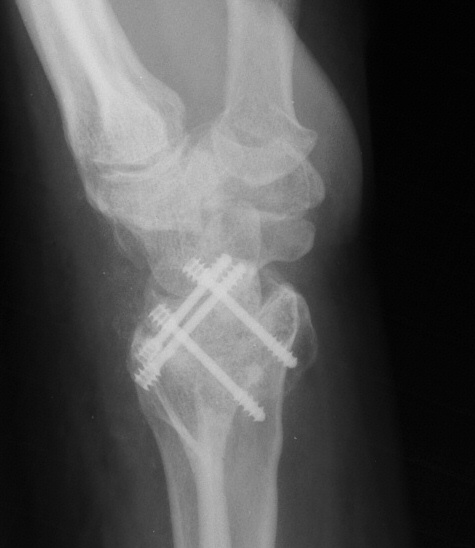

Three months postop :

Radioscapholunate fusion is a treatment option for radiocarpal arthritis following distal radius fracture or associated with rheumatoid arthritis. Range of motion is usually less than half of normal following this procedure. Technical modifications to improve range of motion include distal scaphoid excision, or as in this case, triquetrum excision and excision of distal ulnar articular surface to manage ulnolunate abutment. There are a variety of fixation techniques. In this case, crossed Herbert screws were used: dorsal carpal bone to palmar radius and dorsal radius to palmar carpal bone.